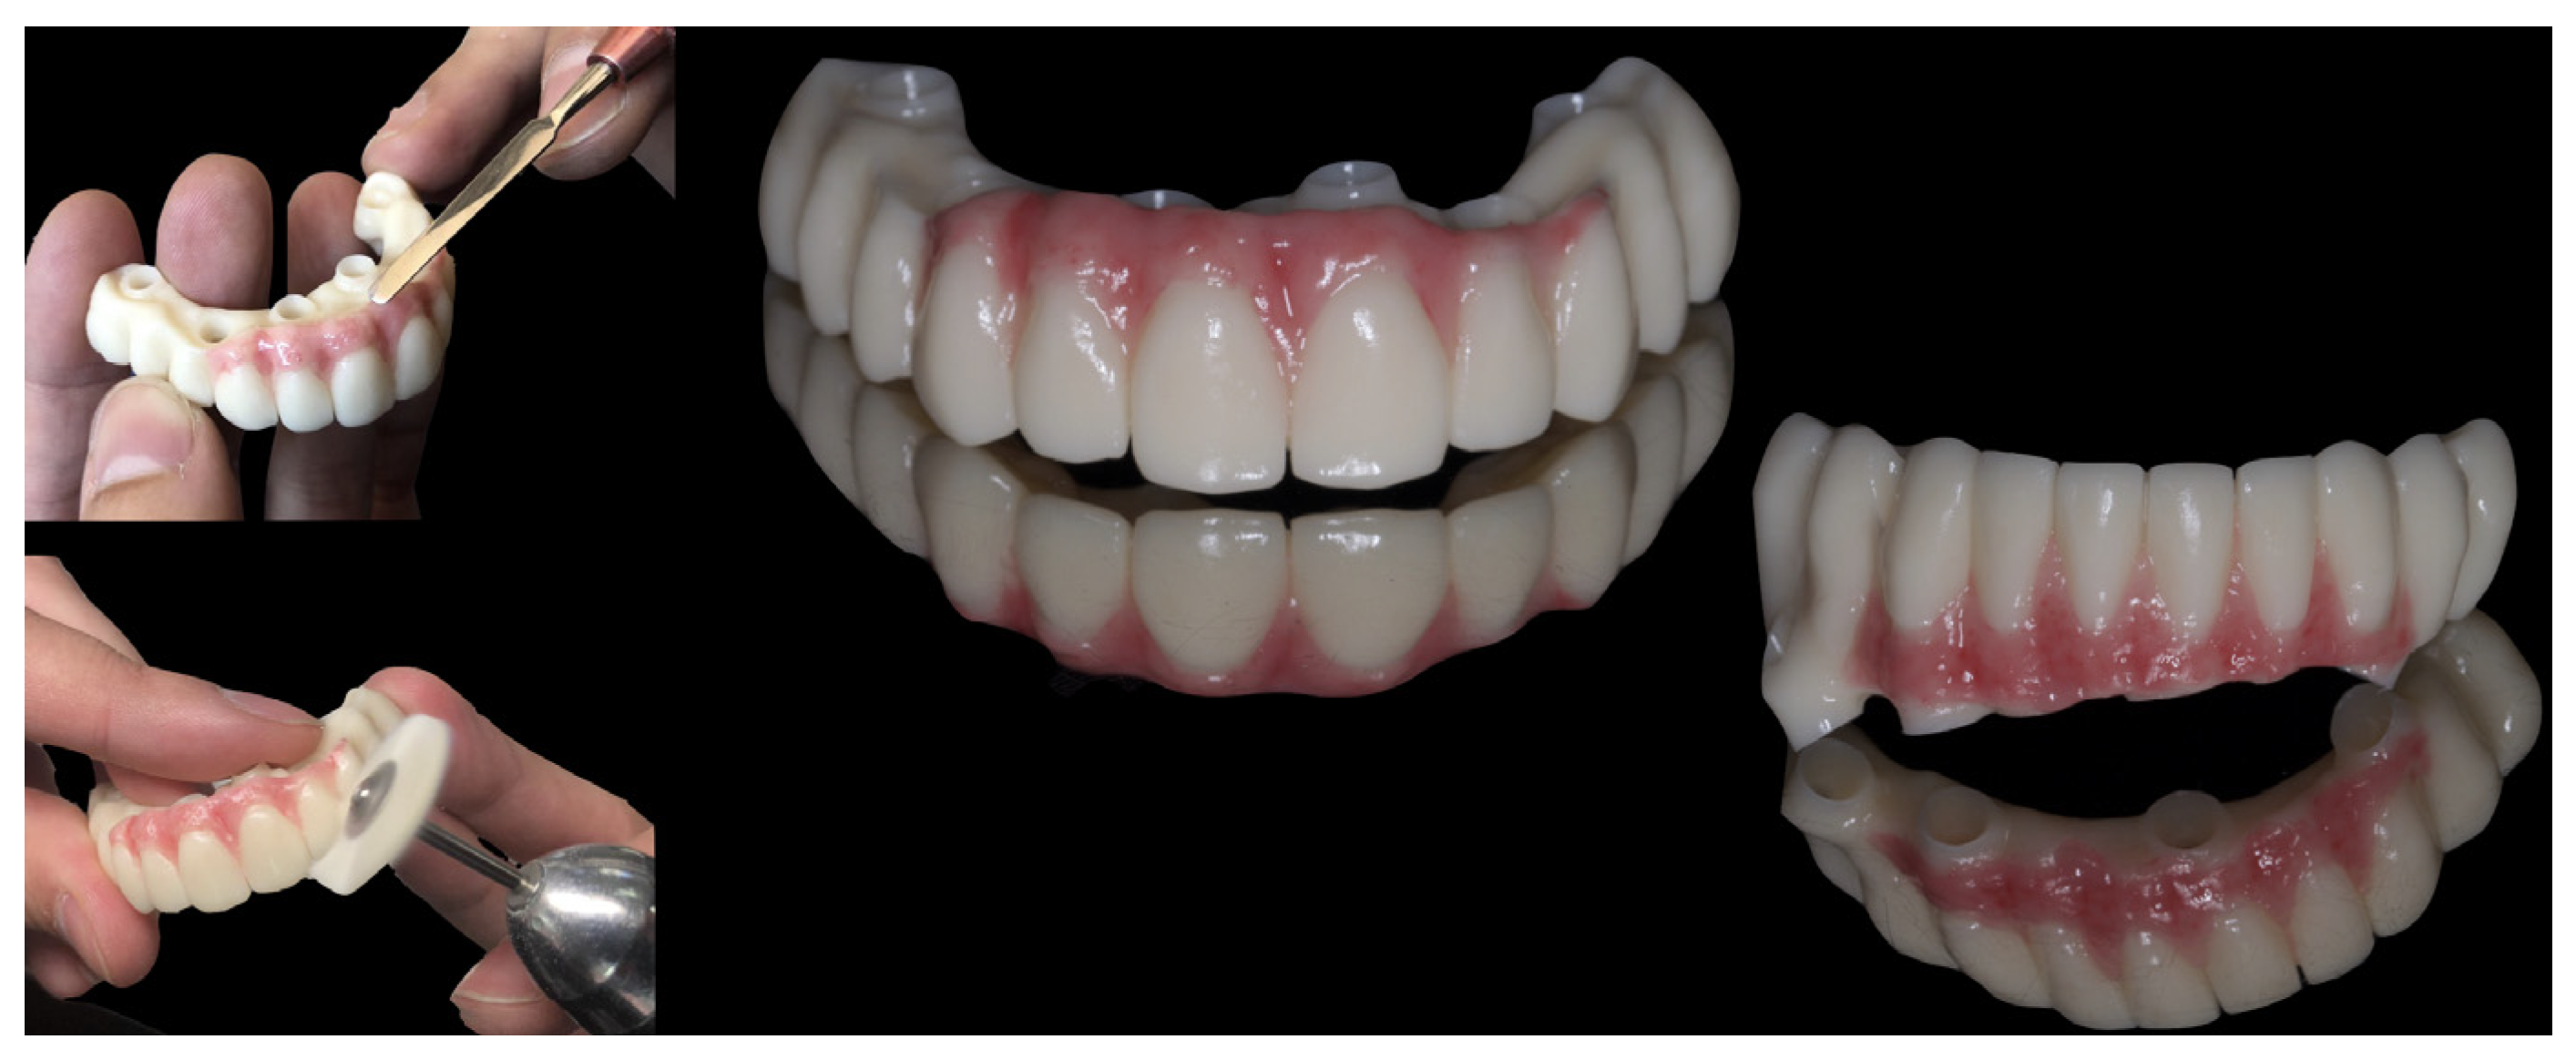

2. Material and Methods